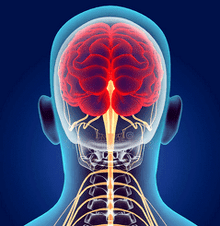

Невелика зміна в одному з хребців викликає здавлення або зміщення нервів і кровоносних судин.Через порушення мозкового кровообігу виникають мігрені, вегето-судинна дистонія та гіпертонія, проблеми з серцево-судинною та дихальною системами, слухом, зором, координацією. У запущеній формі шийний остеохондроз може призвести до синдрому хребетної артерії. Хребтова артерія кровопостачає довгастий мозок і мозочок. При здавленні артерії може розвинутися ішемія головного і спинного мозку, виникнути спінальний інсульт.

Остеохондроз шиї призводить до ураження нервових корінців - утворення наростів на хребцях, часткової або повної втрати рухливості. Найважчим наслідком шийного остеохондрозу є здавлення спинного мозку, яке може призвести до летального результату. Серйозних наслідків можна уникнути, якщо вчасно почати лікування захворювання.